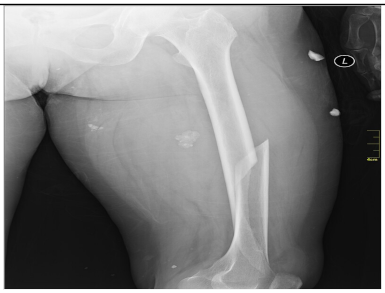

2.6.1. Test Procedure

The stress test involved simulating varying numbers of concurrent users querying the system. For each LLM, we executed 20 clinically relevant prompts, as shown in (Table A2) in the Appendix A. For each VLM, 10 different images with 2 prompts per image resulting in a total of 20 prompts per model were tested. The specific prompts used are listed in (Table A3) in the Appendix A. We tested user loads of 10, 20, 30, 40, 50, 75, 100, 125, and 150 users. In order to measure the robustness of the container as well as the robustness of JAVIS, this experiment queried the JAVIS back-end to measure the complete roundtrip response times. This approach ensured that the test accurately reflected real-world usage scenarios, including the overhead of back-end processing and model orchestration.